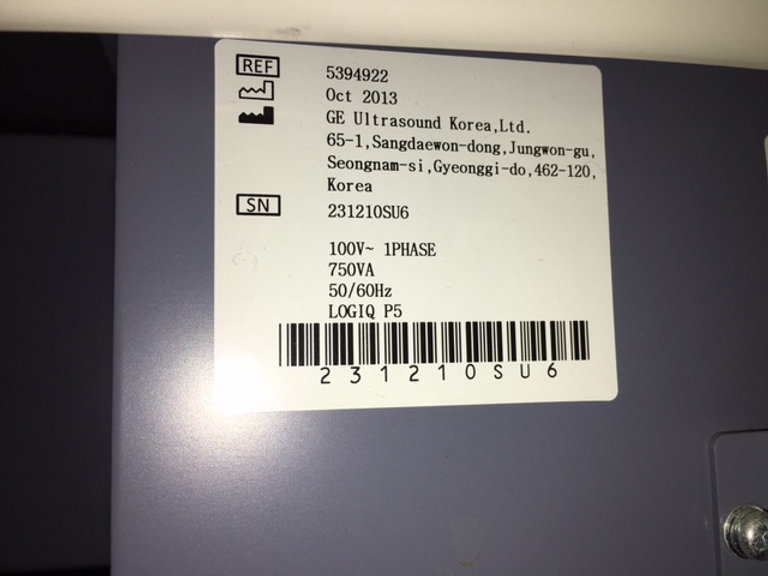

GE Logiq P5 d’occasion Lieu : Australie (U3075) Fabriqué : Oct 2013 Version du logiciel : R4.0.6 Options installées : Basic, Anatomical M, Cross Beam, SRI, Auto Sondes IMT : 5Sp, 8C, 11L